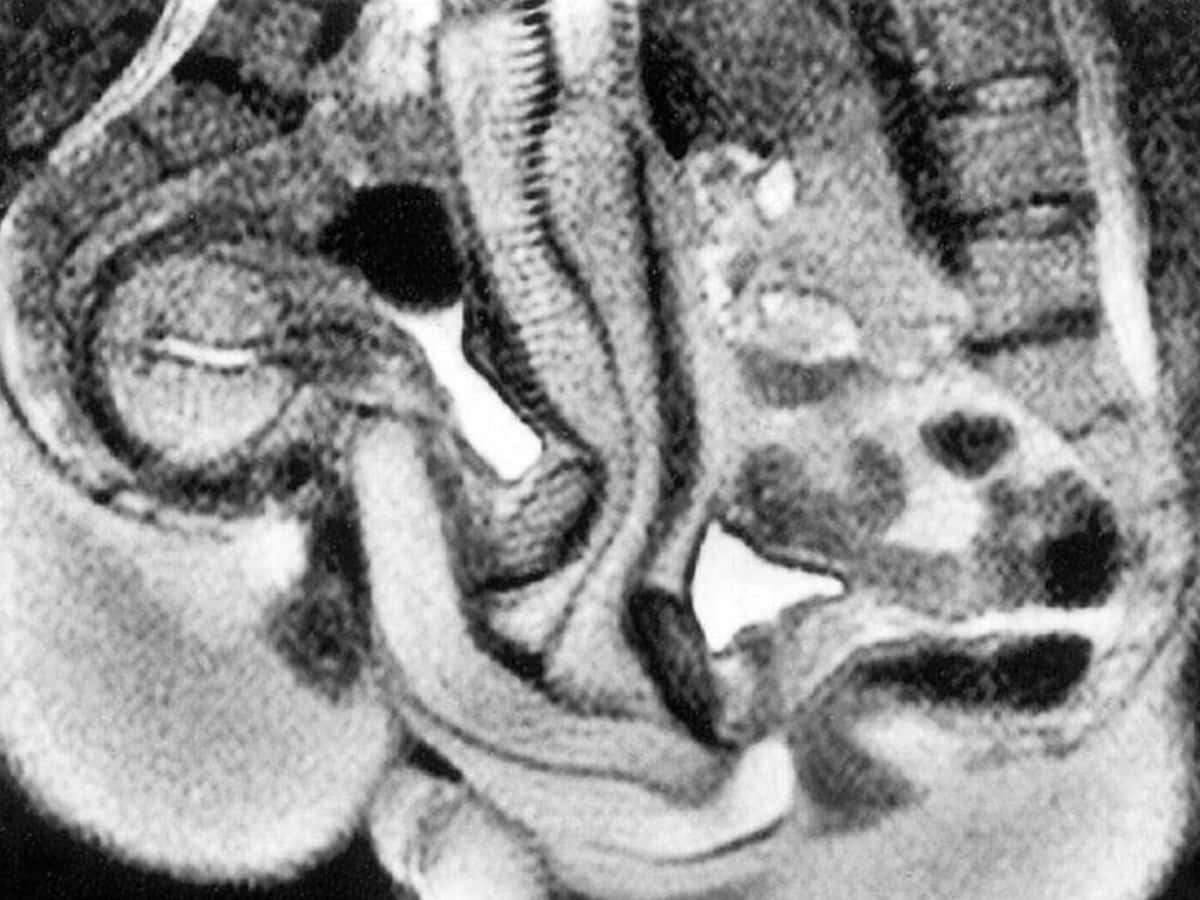

Η πιο σημαντική διαπίστωση της μελέτης αφορά το σχήμα του ανδρικού μορίου. Μέχρι τότε, η επικρατούσα θεωρία ήθελε το πέος να παραμένει ευθύ ή σε σχήμα “S”. Οι εικόνες από τον μαγνητικό τομογράφο όμως έδειξαν κάτι εντελώς διαφορετικό.

Το σχήμα μπούμερανγκ: Κατά τη διάρκεια της διείσδυσης στην ιεραποστολική στάση… Το ανδρικό μόριο καμπυλώνεται σημαντικά για να προσαρμοστεί στη φυσική κλίση του κόλπου.

Η ρίζα του πέους: Αποκαλύφθηκε ότι περίπου το 1/3 του συνολικού μήκους του οργάνου βρίσκεται εσωτερικά στο σώμα, αποτελώντας τη «ρίζα» που του επιτρέπει αυτή την ευελιξία.

Προσαρμογή του κόλπου: Ο γυναικείος κόλπος δεν είναι ένας ευθύς σωλήνας, αλλά αλλάζει σχήμα και έκταση… Με τη μήτρα να ανασηκώνεται μάλιστα κατά τη διάρκεια της διέγερσης.